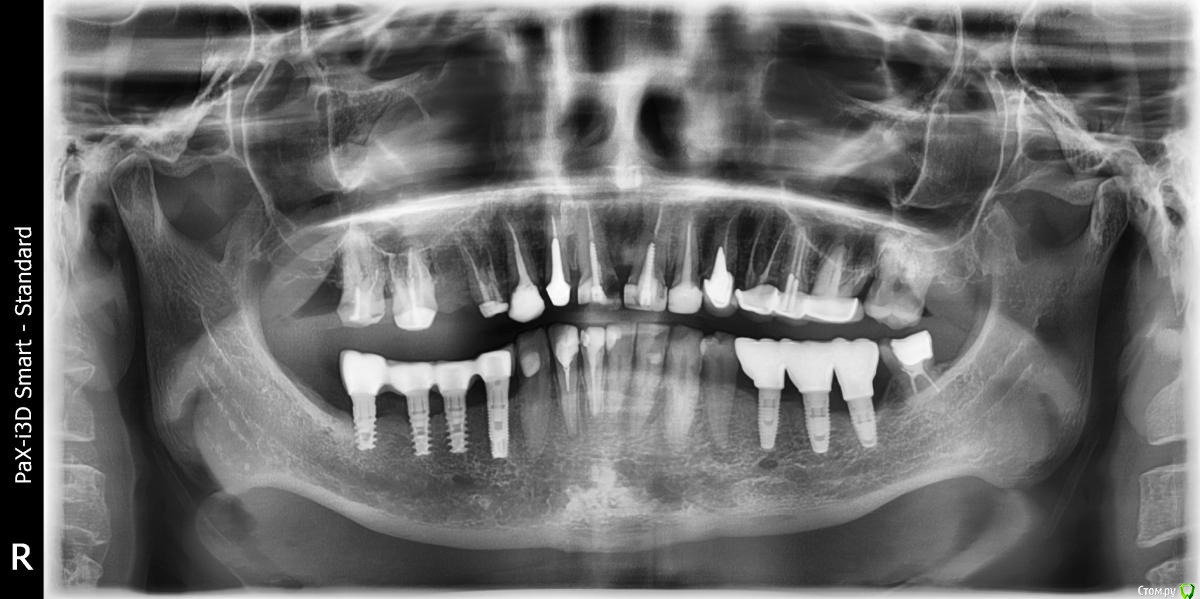

Bagirano Опубликовано 5 февраля, 2020 Поделиться Опубликовано 5 февраля, 2020 Добрый день! Вопрос про 14-17 зубы. Стояло два моста (14-15 и 16-17), 15 зуб сломался и восстановлению не подлежал, его удалила. Второй мост тоже был давний и случайно снялся при удалении. Предлагаемые варианты: 1) цельноциркониевый мост на 4 зуба, 14-17 (лучше в смысле био, обтачивать меньше и, если 14 зуб сломается, мост можно будет распилить и хотя бы две крайний коронки останутся) - около 75 тыс. 2) металлокерамический мост на 5 зубов, 13-17, причем 14 зуб, скорее всего, тоже под удаление (14 совсем ненадежен, рисково вообще его использовать, а тем более как опорный, да и 16-17 не слишком хорошие, возможно, там киста, 13 тоже сплошная пломба, зубы все равно уже все обточенные, бог знает, сколько простоит, нет смысла переплачивать) - около 50 тыс. При этом мне очевидно, что больше пяти лет это богатство не простоит, какой-то из зубов точно разрушится, а то и не один (то же самое происходило и с нижними зубами: лечение, коронки, разрушение, удаление). То есть, по-любому, через 5-7 лет надо будет ставить импланты. Что бы вы выбрали в такой ситуации?Снимок прилагаю. Спасибо! Ссылка на комментарий